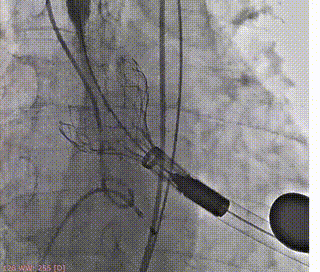

支撑臂释放后定位

瓣叶交界贴合释放瓣膜